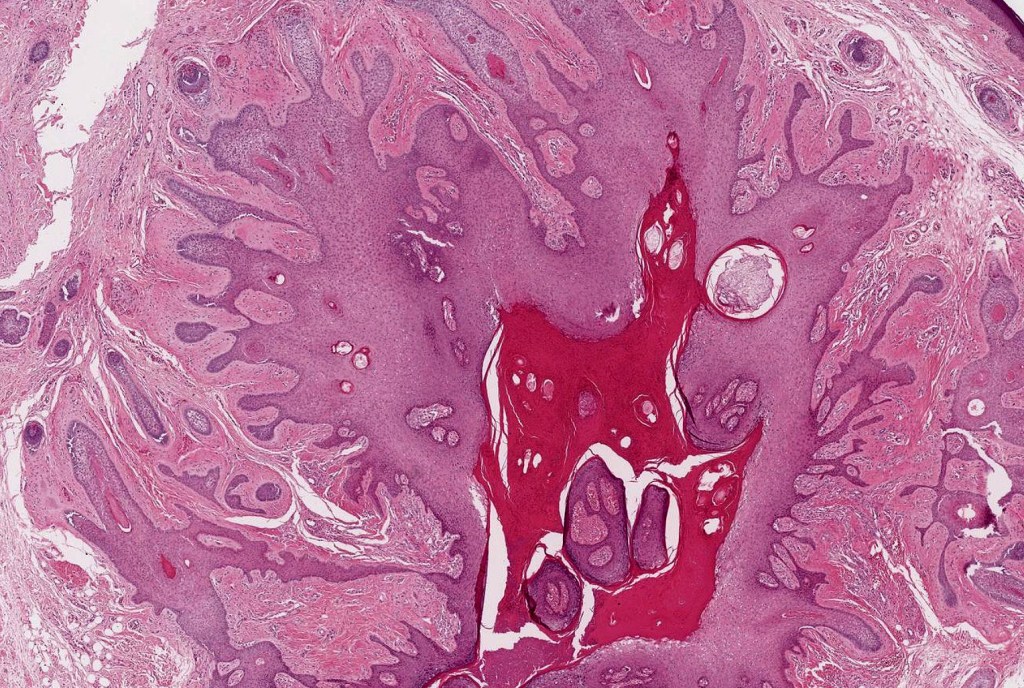

•Circumscribed dermal nodule with a characteristic silhouette

•An infundibular cyst is surrounded by laminated dermal collagen, elastic fibers, blood vessels, adipocytes & spindle cells separated from the adjacent dermis by a retraction artifact

•The cyst contains keratinous debris, and its wall shows conspicuous sebaceous & sometimes hair follicular elements are also evident